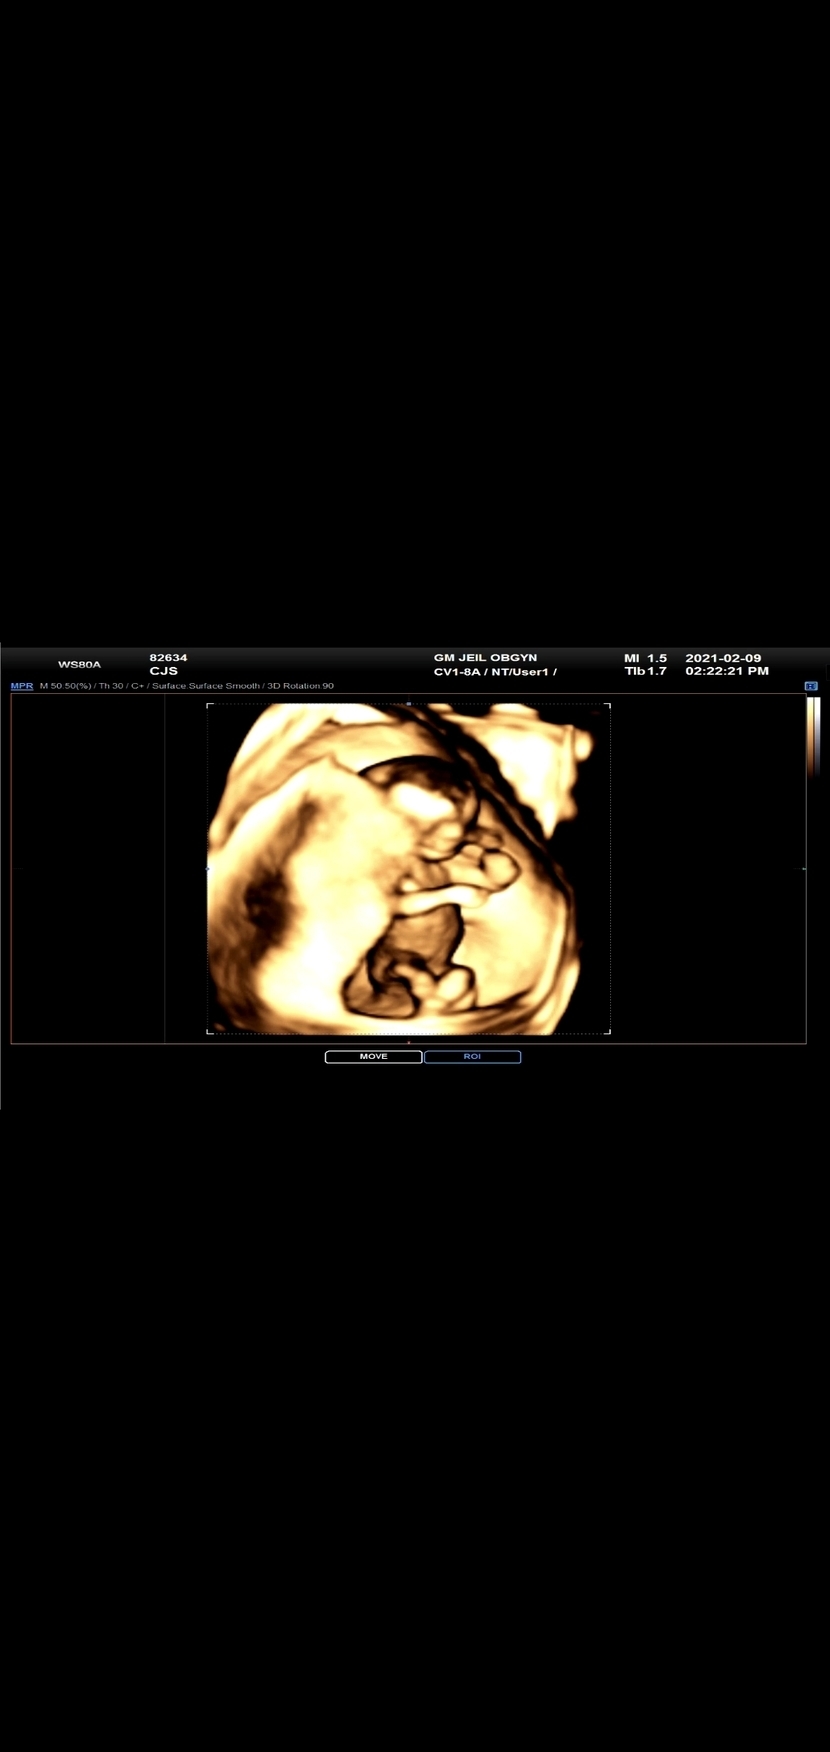

우리 기특이

mongshelltt